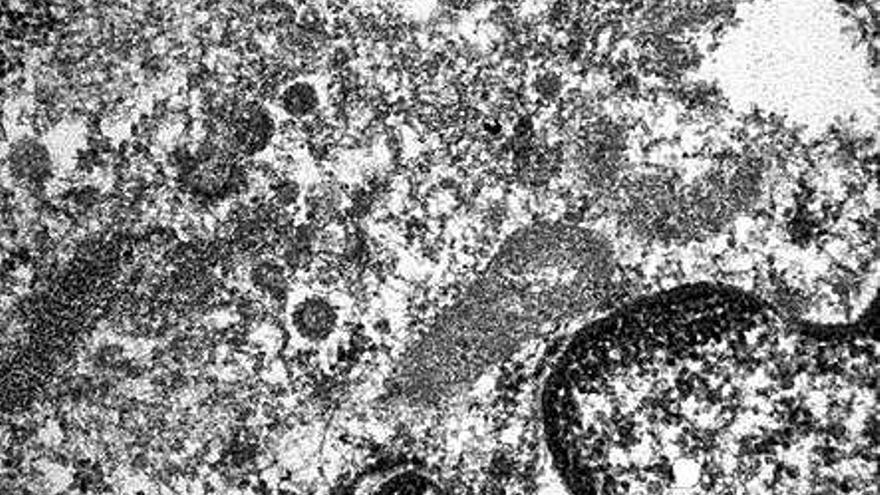

Una micrografia electrònica (és a dir, realitzada amb un microscopi) a l'Hospital del Mar de Barcelona mostra el coronavirus en una zona danyada de l'intestí d'un pacient afectat per la covid-19.

La imatge, que ha estat presa pel doctor Josep Lloreta, integrant del Servei de Patologia, permet veure una part del nucli i citoplasma (que envolta el nucli) de les cèl·lules endotelials que recobreixen els vasos sanguinis per dins.

És principalment al citoplasma d'aquestes cèl·lules on el SARS-CoV-2 es reprodueix i des d'on colonitza la resta de l'organisme. En general, aquests tipus de virus no formen afegits, sinó que més aviat es disposen de manera individual en relació amb el reticle endoplasmàtic rugós de la cèl·lula endotelial.

Aquesta micrografia electrònica, augmentada per 34.000 en relació amb la seva mida original, permet veure diverses partícules víriques amb els traços típics de coronavirus, envoltades per un espai clar.